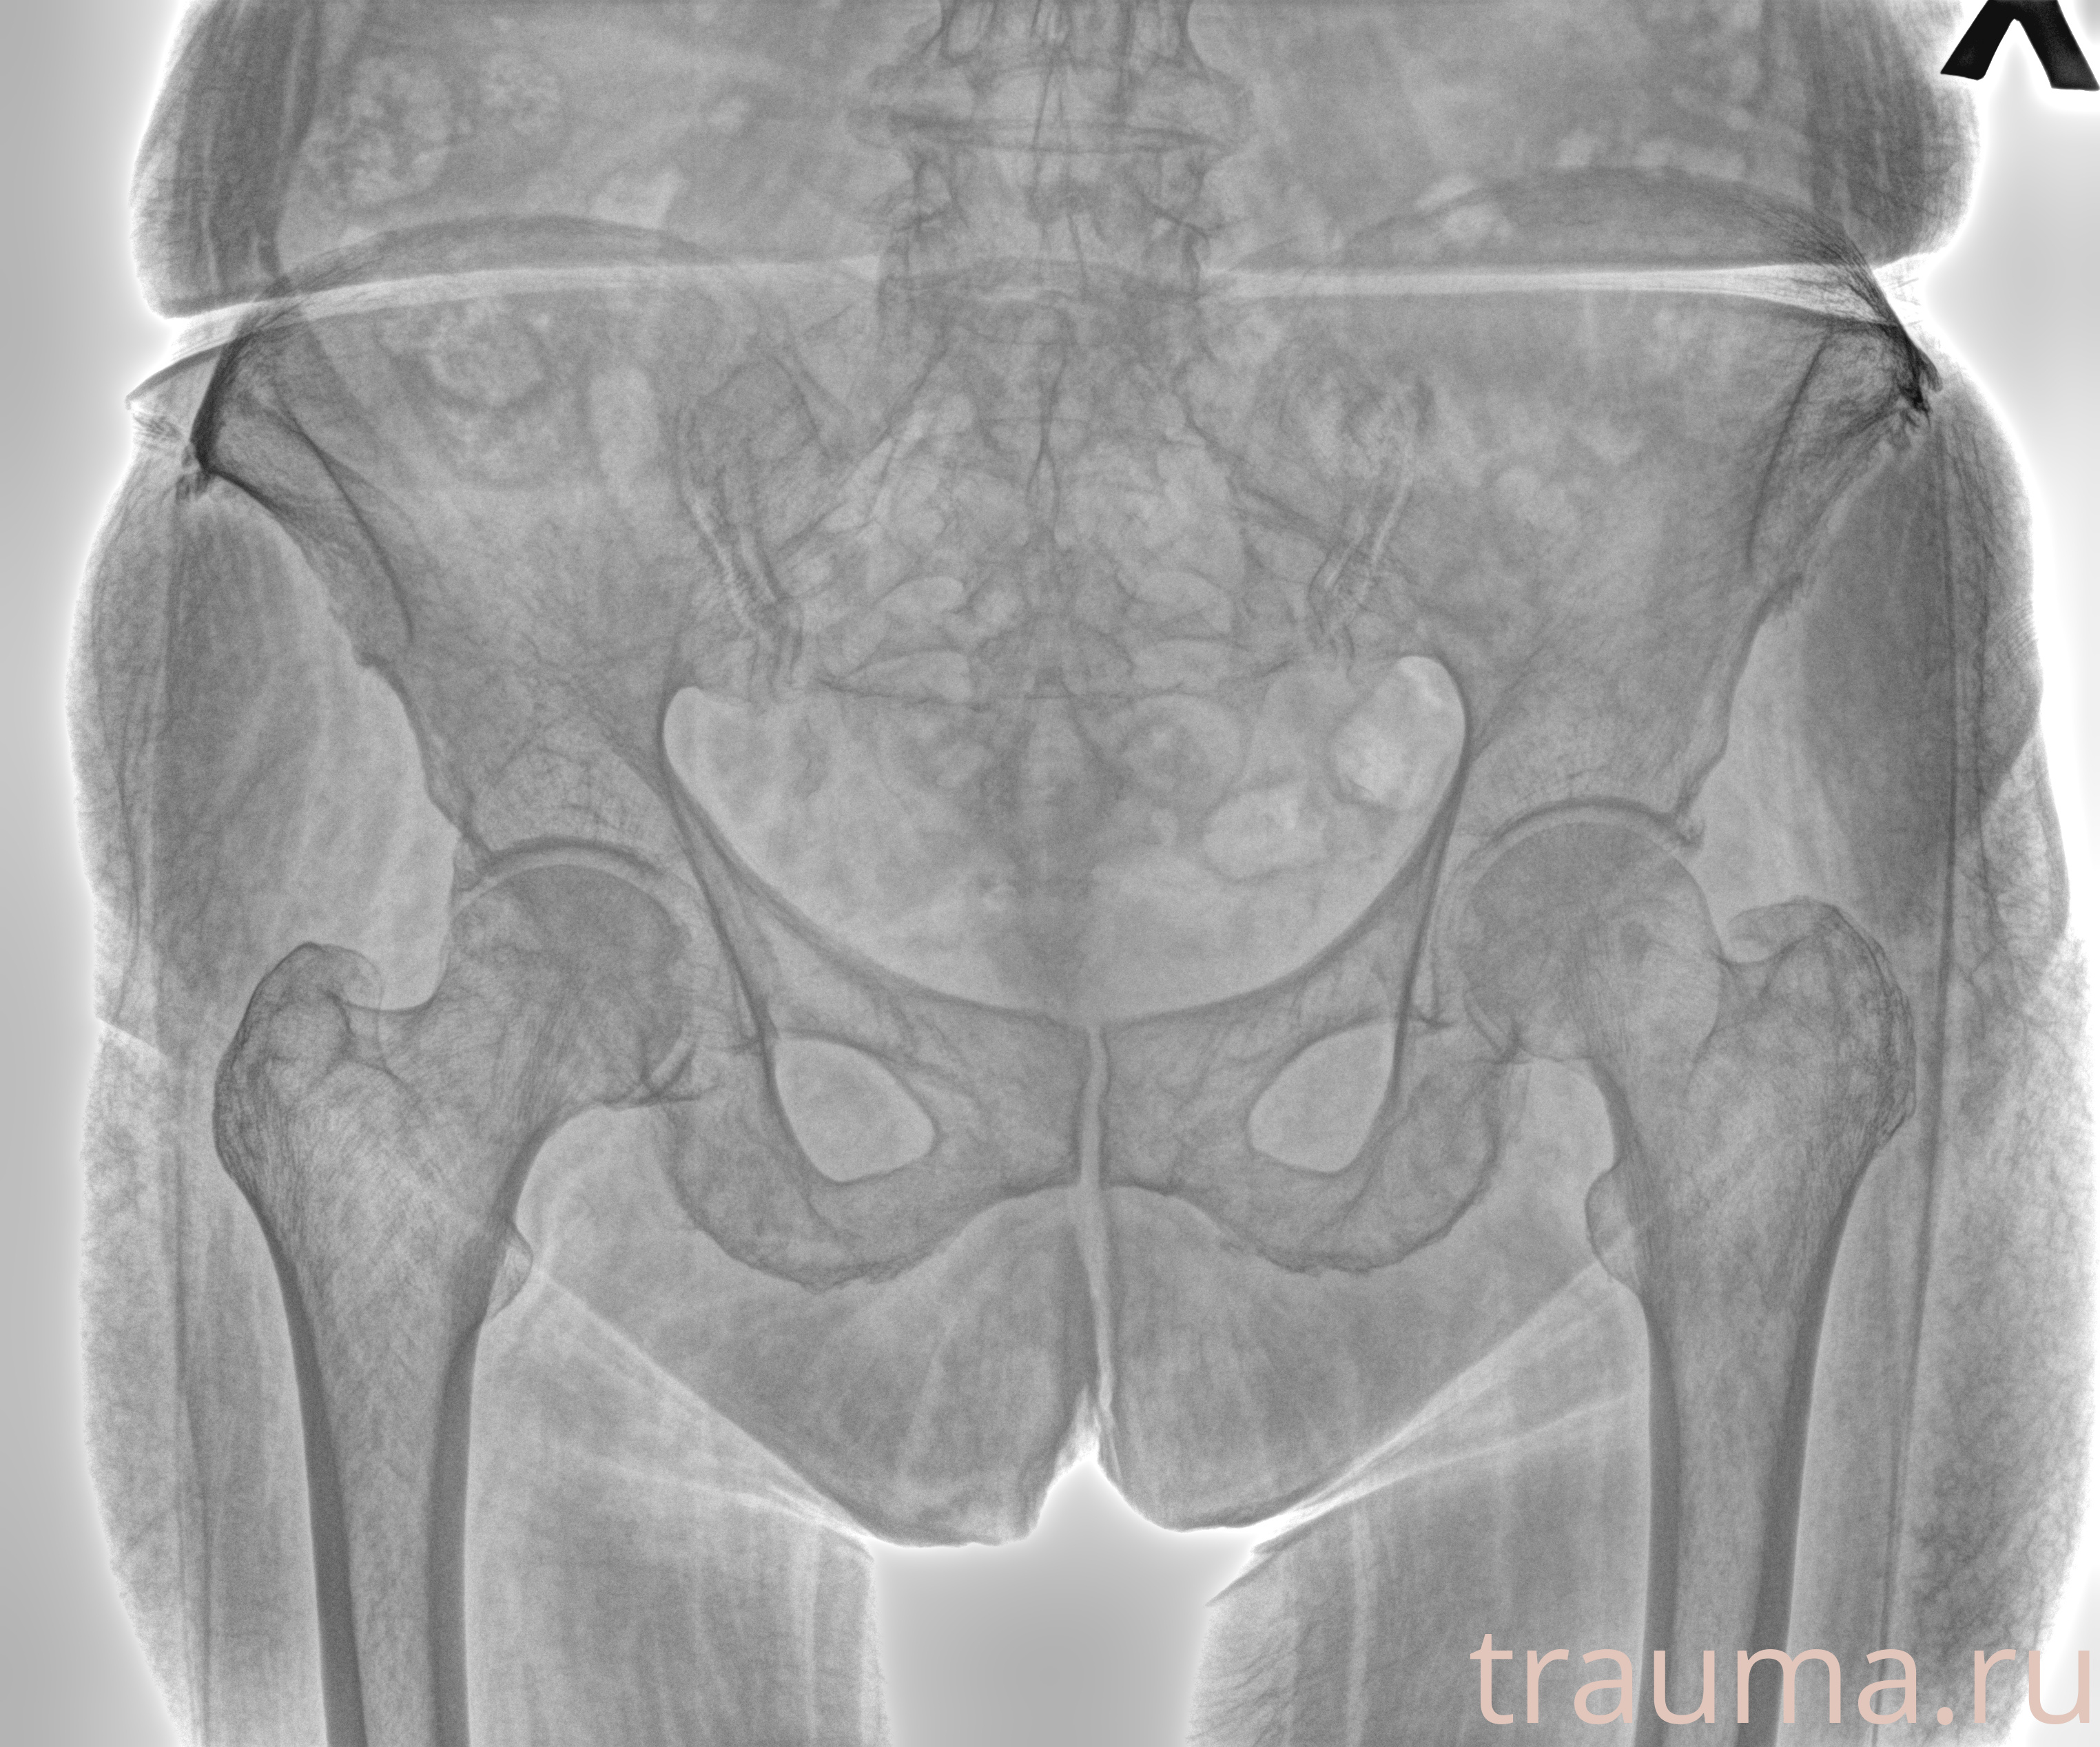

Рентгенограммы

Рентген на дому: по вашему адресу приезжает врач-рентгенолог, травматолог-ортопед с мобильным рентгеновским аппаратом, проводит диагностику травмы или заболевания, делает необходимые рентгенограммы, дает рекомендации по дальнейшему лечению. Получить качественные снимки в домашних условиях возможно благодаря уникальной методике, разработанной МосРентген Центром для института  Склифосовского